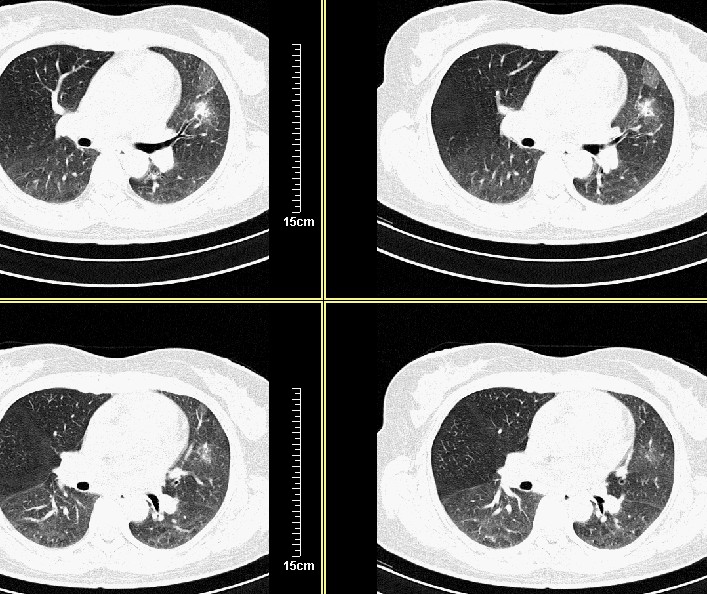

3天后复查:病变明显好转、吸收:考虑炎症可能性大

支气管注药后3天后复查:病变明显好转、吸收:考虑炎症可能性大.

3天后复查:病变明显好转、吸收:考虑炎症可能性大.肿瘤待排

才三天的时间,病灶明显吸收,还是支持炎症,可继续治疗复查。

病灶似乎呈片样,密度不均匀,3天后复查:病变明显好转、吸收:考虑炎症可能性大 。

气管注药后3天后复查:病变明显好转、吸收:考虑炎症可能性大,肺癌待排!